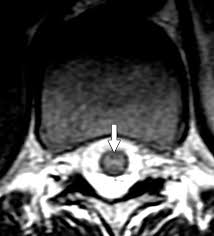

owl eye sign

spinal cord infarct

anterior horn cells

can also be seen in ALS, polio